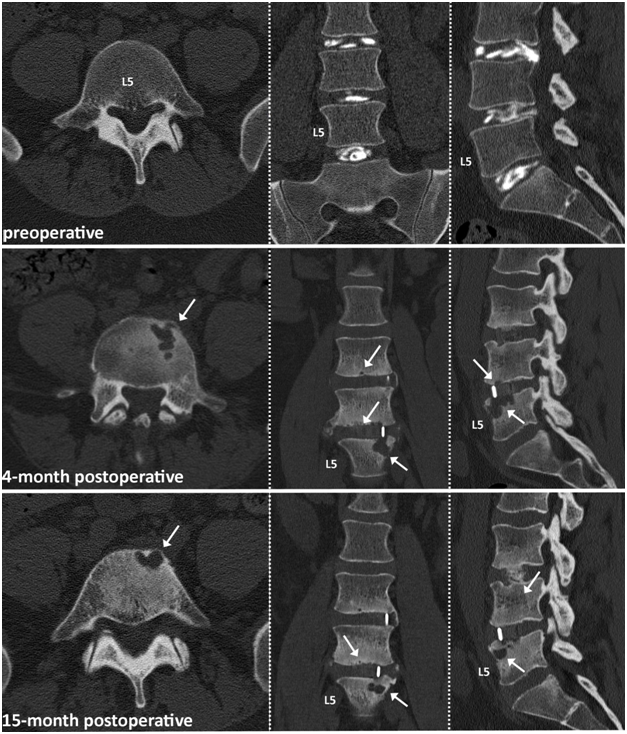

The main highlighted case reports on a 33-year old patient who underwent 2-level standalone LLIF (L3-L5), augmented with 6 mg BMP-2 per level. CT images at 4-months and 15-months postoperatively are shown and depict osteolytic bone destruction affecting the L5 vertebral endplate potentially related to the utilization of BMP-2 (Figure 1). Stability was not preserved and posterior instrumentation was required at the L4-L5 level 16 months after the initial surgery.

Figure 1 33-year old male patient with 2 level LLIF procedure at L4-5. White arrows indicating osteolytic bone destruction starting at the L5 vertebral endplate slightly improving after 15 months of watchful waiting.